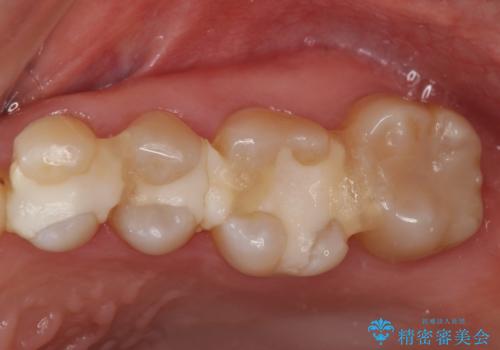

3本仮づめのまま放置 セラミックインレーへ

- 他院で治療途中で放置したところを治療したいとご来院されました。

仮づめはフロスもできないため、不潔になりやすく長期的には虫歯になりやすいです。

目立たない白いものがご希望とのことで、セラミックインレーで修復しました。

仮づめの状態でしたが、そこまで中は虫歯になっておらず、神経の治療も不要でした。